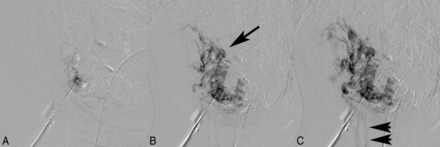

Early (A), mid (B), and late (C) phase direct needle puncture phlebography of a left facial venous malformation by using a traditional digital subtraction angiography technique shows appropriate needle localization for subsequent embolization. There is satisfactory sequential opacification of the venous channels of the lesion (arrow) and only faint flow into small draining veins (arrowheads), with no evidence of contrast extravasation or demonstration of large draining veins.